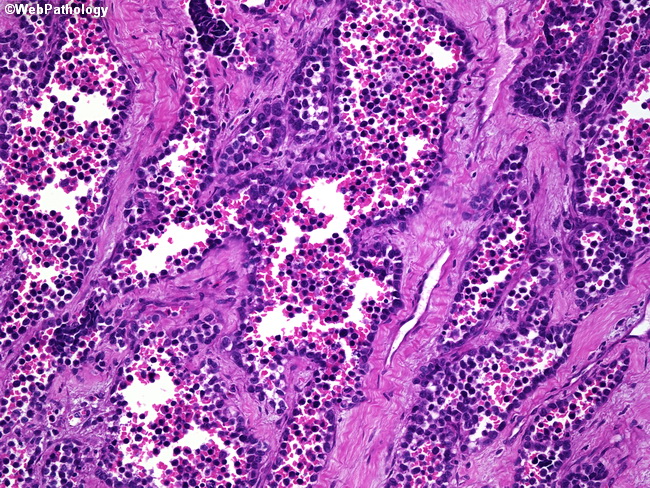

Soft Tissues: Alveolar Rhabdomyosarcoma

Webpathology.com: A Collection Of Surgical Pathology Images

rhabdomyosarcoma alveolar webpathology pathology

Webpathology.com: A Collection Of Surgical Pathology Images

rhabdomyosarcoma alveolar webpathology pathology comments microscopic

Webpathology.com: A Collection Of Surgical Pathology Images

rhabdomyosarcoma webpathology

Webpathology.com: A Collection Of Surgical Pathology Images

rhabdomyosarcoma alveolar webpathology